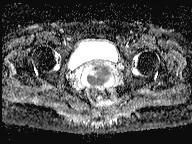

轴位

DWI

此外,肿瘤还累及宫旁组织。影像学检查发现异常淋巴结肿大,最大短轴直径(SAD)为10 mm,位于髂总血管分叉处和髂内动脉链下方。该淋巴结肿大在弥散加权成像(DWI)上显示水限制,且增强扫描后可见强化。